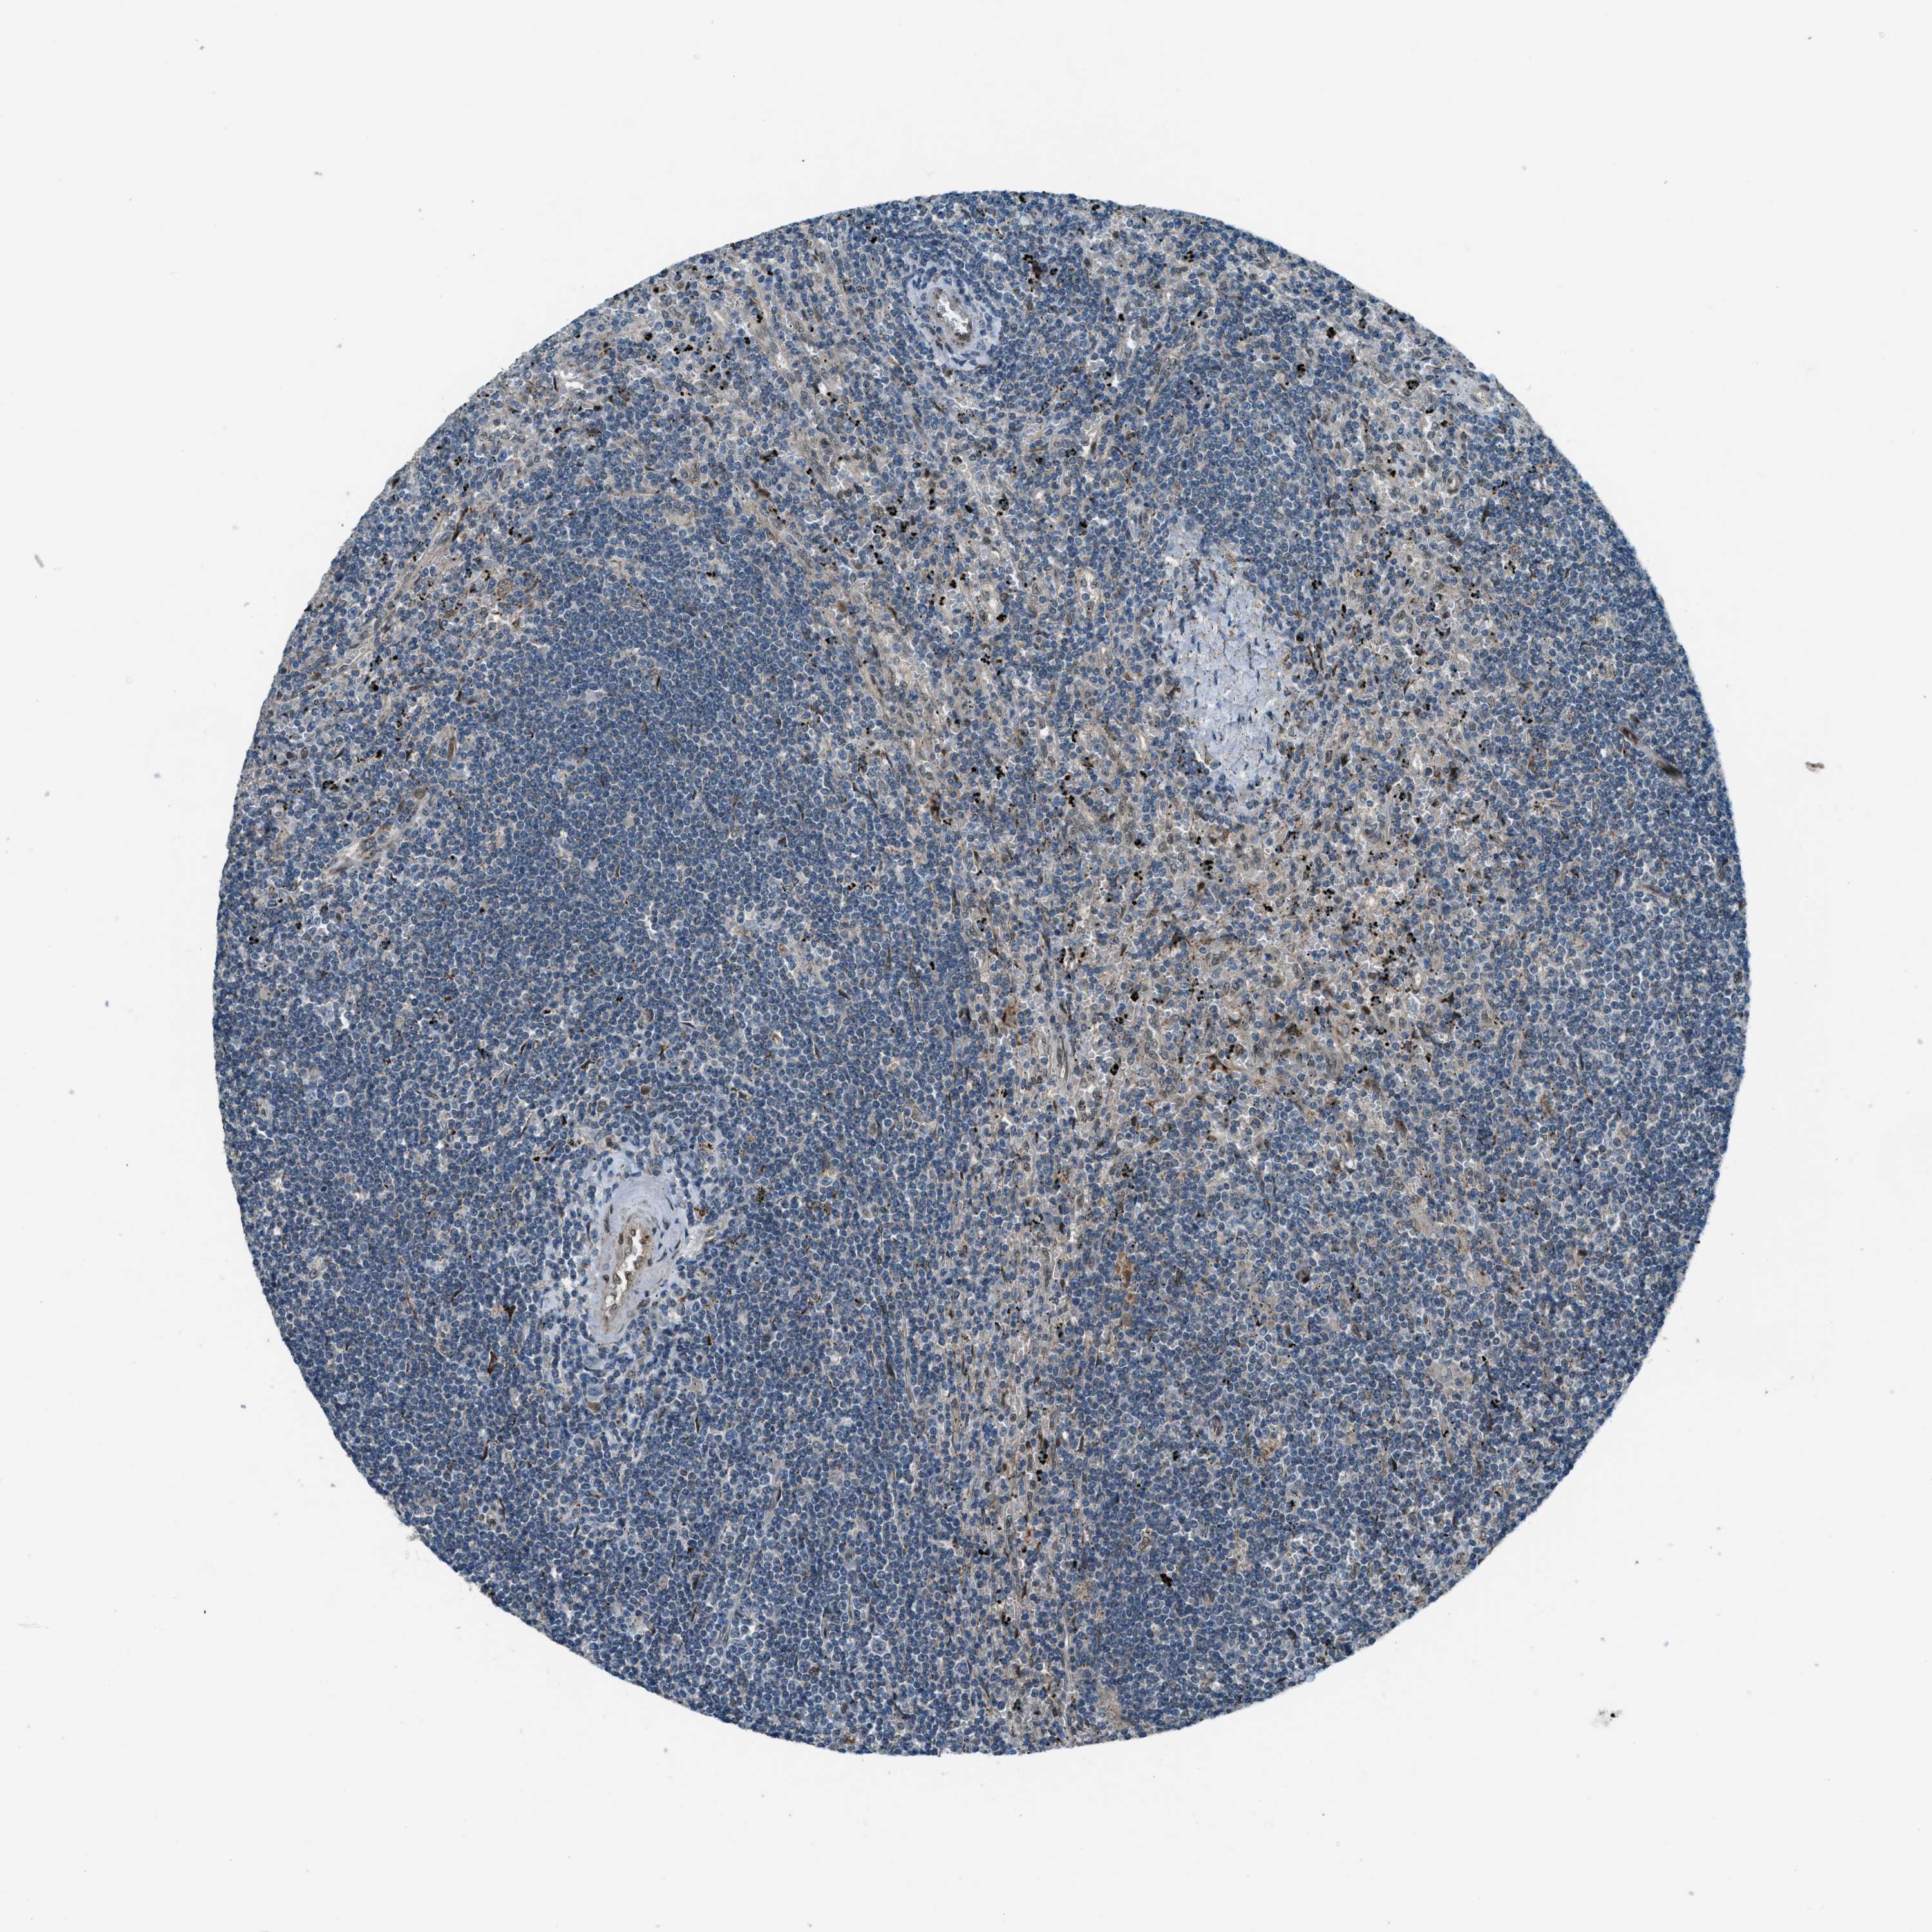

CANCER LYMPHOMA Show tissue menu

LYMPHOMA - Protein expressioni

A mouse-over function shows sample information and annotation data. Click on an image to view it in a full screen mode. Samples can be filtered based on level of antibody staining by selecting one or several of the following categories: high, medium, low and not detected. The assay and annotation is described here.

Each image is clickable and will lead to virtual microscopy that enables deeper exploration of all samples and also displays staining intensity scores, fraction scores and subcellular localization as well as patient and tissue information for each sample.

Antibody HPA036356

Antibody CAB004986

Antibody CAB017025

Hodgkin's disease, NOS

Malignant lymphoma, non-Hodgkin's type, High grade

Malignant lymphoma, non-Hodgkin's type, Low grade